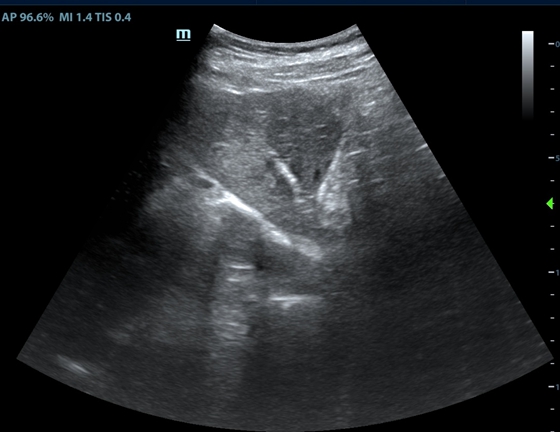

手术在胡康新教授的指导下进行,由汤金城医师、黄彬副主任医师共同为患者实施了微波消融术。患者局部麻醉后,在B超定位下准确刺中左肝病灶,动态消融7分钟,退出消融针后再次B超探查发现左肝另一低回声信号结节,故再次进行动态监测下消融4分钟。术中患者并无明显不适,术后安全返回病房。